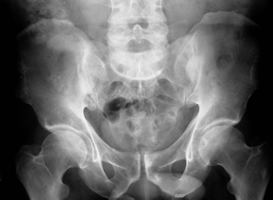

Die Verletzung ist folgenlos ausgeheilt. Die Patientin ist beschwerdefrei.